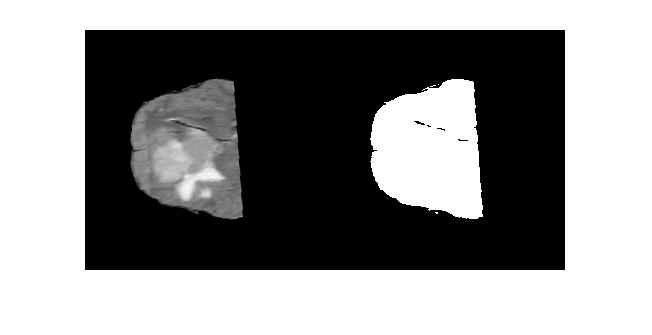

imshowpair(IM,bin_mask1,'montage')灰谷结果:

多重阈值结果: